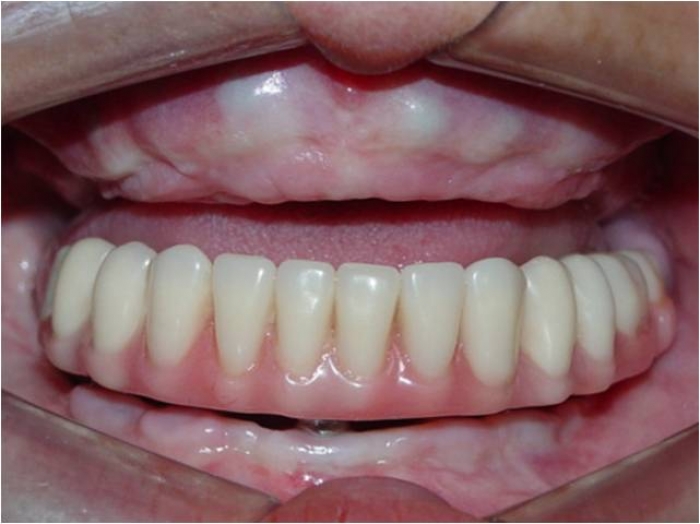

Prótese fixa provisória inferior - Clínica Cliniface

Prótese fixa provisória inferior